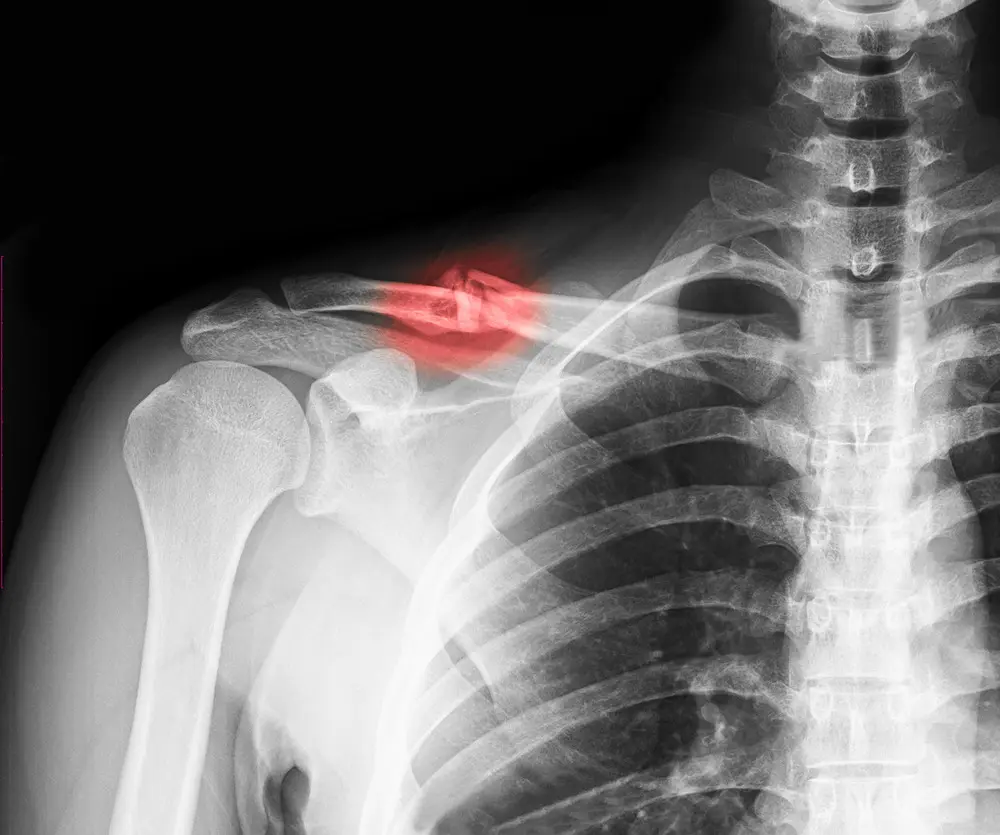

A fracture of the shoulder socket, also called a glenoid fracture, is a break in the glenoid, the shallow, cup-shaped part of the shoulder blade (scapula) that forms the socket of the shoulder joint.

Because glenoid fractures can affect shoulder stability and long-term joint function, prompt medical evaluation and imaging (X-ray or CT scan) are important for proper diagnosis and treatment.